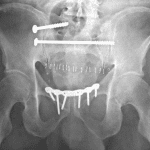

- Unstable pelvic ring injury (APC II)

Unstable pelvic ring injury with diastasis of the pubic symphysis measuring up to 3 cm and mild widening of the right sacroiliac joint.

- It is important to be able to recognize unstable pelvic injuries because this impacts immediate patient management (pelvic binders are typically placed before the patient even goes for CT imaging)